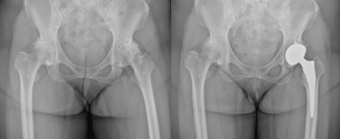

変形性関節症や骨壊死などによって傷んだ関節の表面を、人工の関節に置き換える手術です。

この手術により、長年続いていた関節の痛みが大幅に軽減され、生活の質(QOL)の改善が期待できます。